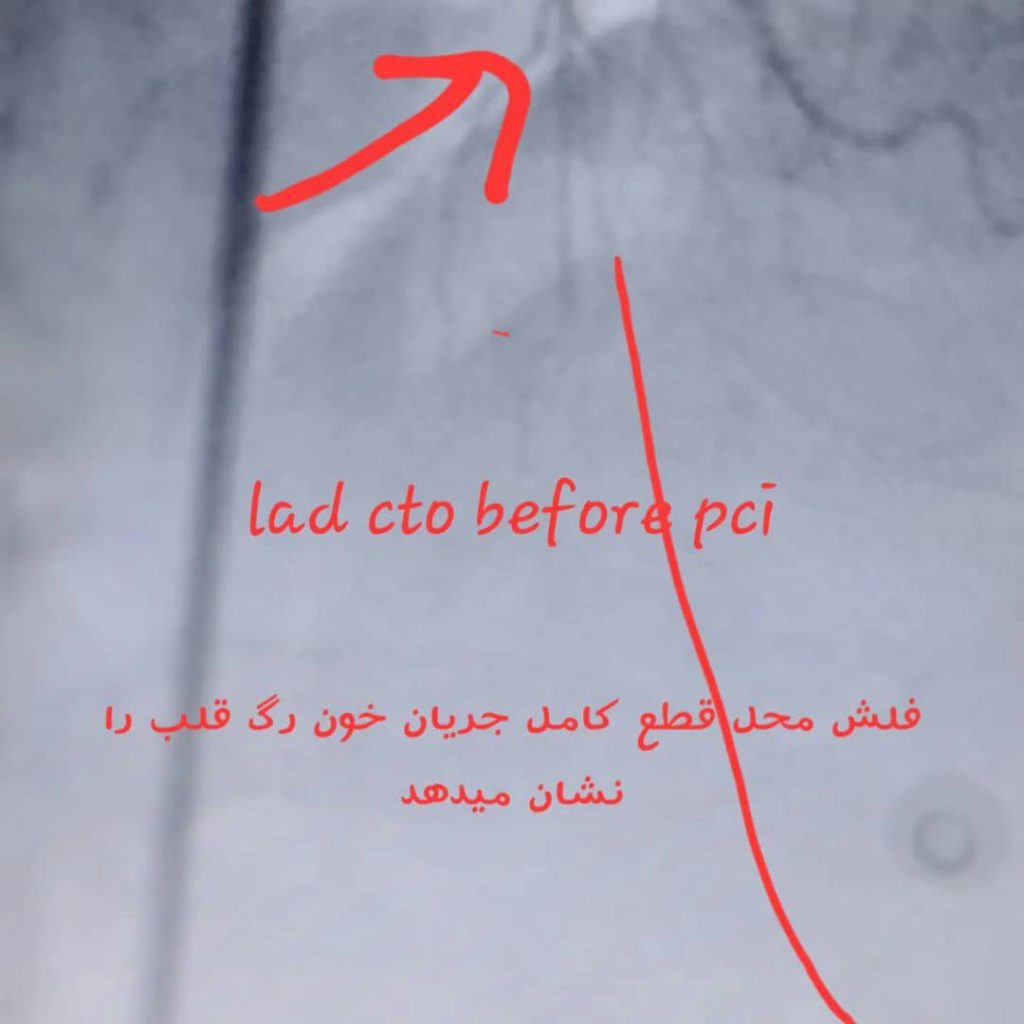

درمان انسداد کامل عروق قلبی بدون نیاز به عمل جراحی باز

آنژیوپلاستی عروق تنگ یا کاملا مسدود قبلی , والووپلاستی